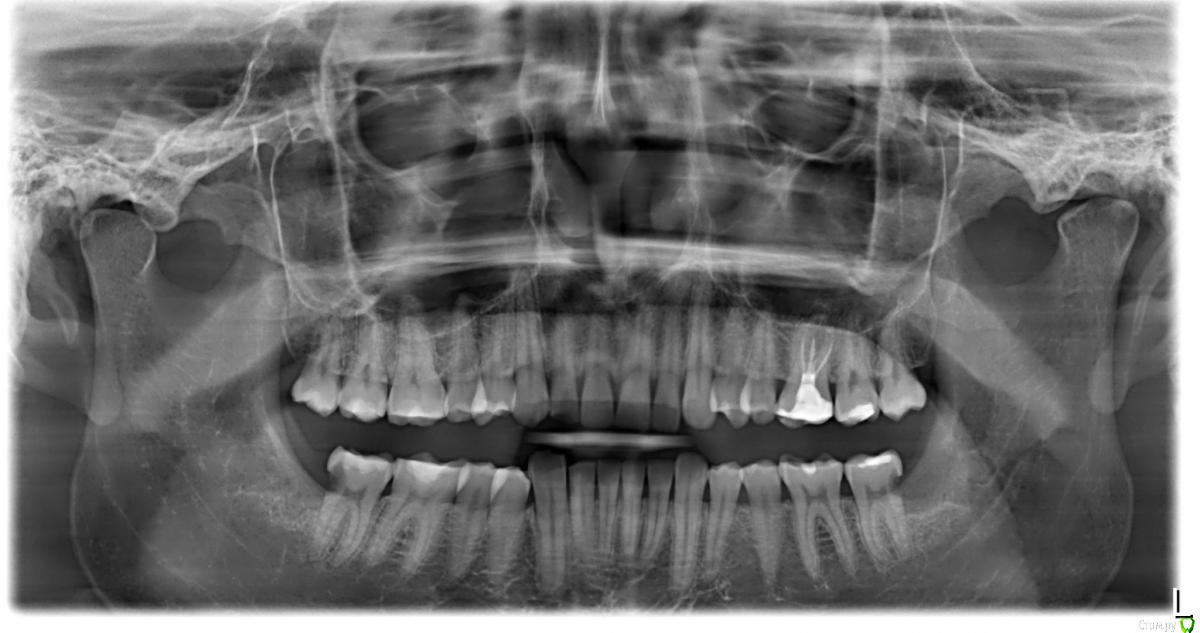

zwz443 Опубликовано 26 сентября, 2018 Поделиться Опубликовано 26 сентября, 2018 (изменено) Здравствуйте подскажите пожалуйста, ,случилась такая проблема, которая не имеет алгоритма появления в целом.Первый раз ел хлеб,и резкая тянущая боль в правой стороне челюсти(словно камень был в хлебе),которая прошла через 5 минут.Следующие разы возникает спонтанно и не всегда, при жевании..или замечал, когда выпить газировку,или съесть сосательные конфеты.Если ничего не есть, боли не происходит, она больше возникает когда происходит полноценное жевание( когда широко раскрывается рот) .Долго не мог понять какой зуб беспокоит,бывает так что отдаёт и в верхний ряд и в целом в правую челюсть.. но с утра часто языком, ощушения на 36 зубе(который справа, 8 удалена, за ним идёт зуб (37) а за ним следующий(36)если я правильно понял),язык упирается в бок зубу и происходит осушение некого холодка.Снимок прикрепил, недавно удалял 8 с другой стороны и сказал доктору об этом, он сказал , что кариеса нету и возможно это происходит из за прикуса ,Который у меня не правильный,но по утрам зуб тоже чувствуется ,когда всю ночь не ел .Осушение что зуб , беспокоит какой то фактор ,после которого он может среагировать на горячие или на слюну.Простите,если так много слов,просто это трудно описать,ни разу с таким ещё не сталкивался. Изменено 26 сентября, 2018 пользователем zwz443 Ссылка на комментарий

red_butler Опубликовано 26 сентября, 2018 Поделиться Опубликовано 26 сентября, 2018 Пульпить обоих седьмых зубов на нижней челюсти Ссылка на комментарий